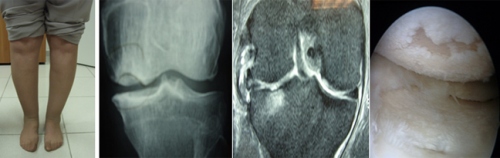

Αρθρίτιδα ονομάζεται η αλλοίωση του χόνδρου των αρθρώσεων. Ο φυσιολογικός χόνδρος είναι ελαστικός, στιλπνός (γυαλιστερός) και έχει μεγάλη αντοχή στις πιέσεις (δεν παραμορφώνεται) γιατί περιέχει πολύ νερό. Όταν για κάποιο λόγο υποστεί τραυματισμό (λόγω ηλικίας, λόγω στραβού άξονα του ποδιού, κ.α.) χάνει τα υγρά κι αρχίζει να εκφυλίζεται (αλλοιώνεται) μέχρι να καταστραφεί εντελώς και ν΄ αφήσει το οστούν (κόκκαλο) της άρθρωσης γυμνό, ακάλυπτο. Τότε έχει εγκατασταθεί πλήρως η αρθρίτιδα. Άρα ο χόνδρος έχει διάφορα στάδια αλλοίωσης. Αρχικά χάνει τη στιλπνάδα και την ελαστικότητά του, κατόπιν αρχίζει να δημιουργεί σκασίματα και τελικά πέφτει κι αφήνει το οστούν ακάλυπτο.

Η θεραπεία αρχίζει να καλύπτεται από τα ασφαλιστικά ταμεία. Είναι σχετικά απλή στην εφαρμογή της. Αρχικά γίνεται λιποαναρρόφηση και αφού ετοιμαστούν τα βλαστοκύτταρα στο εργαστήριο, μετά 5-10 ημέρες ή ενίονται με ακτινολογική παρακολούθηση στο ισχίο ή το γόνατο ή γίνεται αρθροσκόπηση και τοποθετούνται με τη μορφή ζέλης. Εξαρτάται από το μέγεθος της βλάβης. Σε χόνδρο που φαίνεται με μαγνητική, να έχει χάσει την στιλπνότητά του, γίνεται ένεση. Όταν έχει χαραγματιές γίνεται ή ένεση ή ζέλη. Όταν έχει αποπέσει, τοποθετούνται με τη μορφή ζέλης αρθροσκοπικά.

Αποτελέσματα νιώθει κανείς μετά το τρίμηνο, οπότε έχουν αναπτυχθεί αρκετά βλαστοκύτταρα κι έχουν δημιουργήσει χονδροκύτταρα. Σαφής βελτίωση υπάρχει στους 12 μήνες, οπότε γίνεται νέα μαγνητική για επιβεβαίωση του αποτελέσματος της θεραπείας.